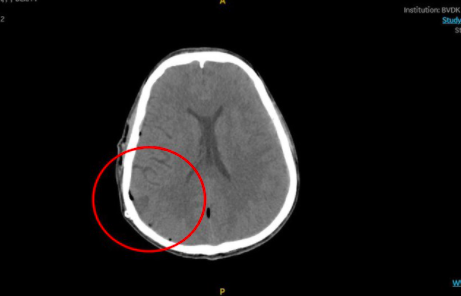

Kết quả chụp CT cho thấy sọ của bệnh nhân có đường nứt nhẹ, xuất huyết não do đứt một mạch máu nhỏ vì chấn thương. Bệnh nhân được đưa vào phòng mổ để cầm máu, hút máu tụ khoảng 150 ml.